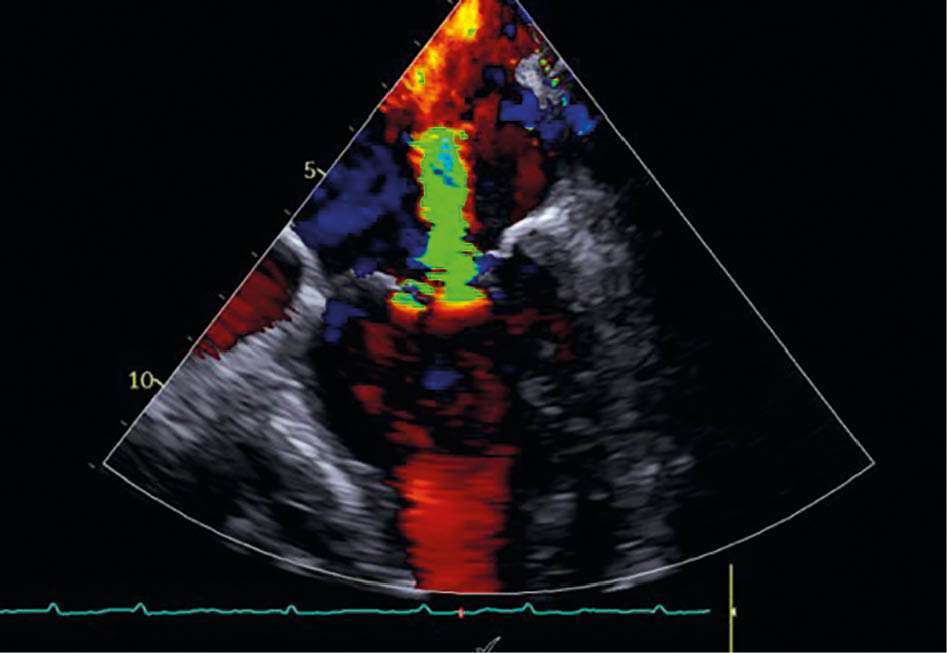

Mitralklappeninsuffizienz in TEE vor der Behandlung

Abbildung 3a: Mitralklappeninsuffizienz in TEE vor der Behandlung

Eine 84-jährige Patientin mit bekannter Herzinsuffizienz bei erhaltener Pumpfunktion (HFpEF, LVEF 50 %) und symptomatischer Belastungsdyspnoe (NYHA III: Treppensteigen nur mit Einschränkungen möglich) wurde in der Klinik vorstellig. Die transthorakale Echokardiographie ergab eine schwere sekundäre Mitralklappeninsuffizienz (effektive Regur­gi­ta­ti­ons­fla­̈che EROA: 0,5 cm2) bei ausgeprägter linksatrialer Dilatation (Volumenindex 64 ml/m2). Als weitere Diagnosen sind eine arterielle Hypertonie und chronisch permanentes Vorhofflimmern bekannt. Die konservative Therapie bestand aus ACE-Hemmer, Betablocker, Schleifendiuretikum und SGLT2-Inhibitor. Trotz maximaler medikamentöser Therapie persistierte eine relevante Symptomlast.

Postinterventionell zeigte sich echokardiografisch eine Reduktion der MI auf Grad 1 mit deutlicher Abnahme des EROA auf 0,1 cm2. Die Patientin berichtete bereits am ersten postinterventionellen Tag über eine deutliche Besserung der Dyspnoe. Die Entlassung erfolgte am zweiten postprozeduralen Tag unter stabilen hämodynamischen Verhältnissen. Die strukturelle Nachsorge ist über den niedergelassenen Kardiologen in enger Zusammenarbeit mit der kardiologischen Klinik organisiert (TTE-Kontrollen nach 1, 3 und 6 Monaten, Laborparameter, 6-Minuten-Gehtest [6MWT]).